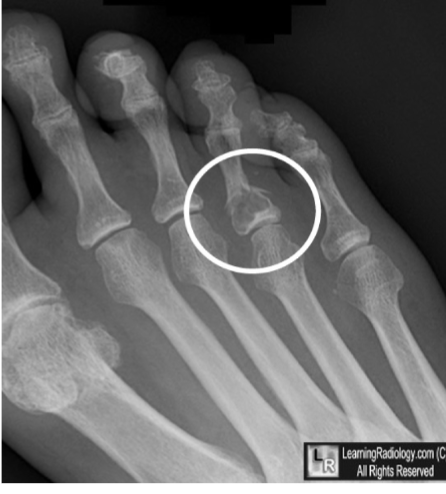

Avulsion Fracture

Occur at site of muscle, tendon, or ligament attachment; from abrupt pull, piece of bone is avulsed with soft tissue